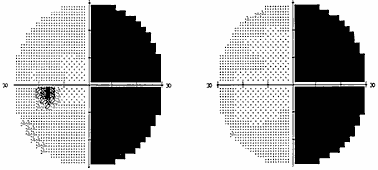

Рис. 2. Полная правосторонняя гомонимная гемианопсия (автоматическая статическая периметрия)

Рис. 3. Начальная левосторонняя гомонимная гемианопсия (автоматическая статическая периметрия)